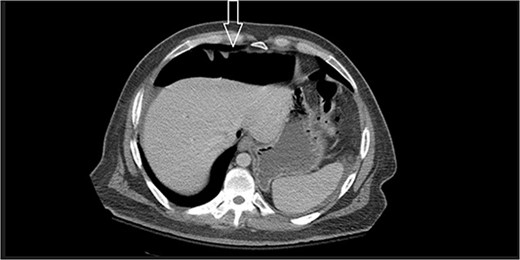

Ten days prior to ER admission, he presented to an outlying hospital with nausea, vomiting and diarrhea episodes and underwent a LC. A baseline computerized tomography scan (CT) demonstrated pneumoperitoneum (see Fig. 1). Because of the lack of inflammatory changes in the GI tract, viscus perforation was an unlikely consideration. An EL was performed that came back negative and he was subsequently discharged.